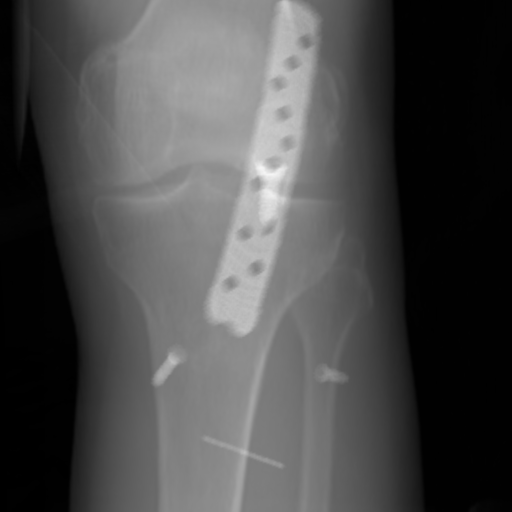

The complementary view setting for learning perspective deformation is also evaluated on real CBCT projection data. In this evaluation, real CBCT projection data from a dataset of knees with metal implants is used for testing, while DRRs created from volumetric CT datasets with inserted metals is used for training. Three exemplary DRR perspective projection images for training are displayed in Fig. 13, in which synthetic metal implants are inserted [34]. The appearance, e.g., image contrast and metal image resolution, of such DRR training images is different from that of real projection images in Fig. 14. In Fig. 14, the results for three knees, with and without metal implants, are displayed. The first and second rows are the 0superscript00^{\circ} and 180superscript180180^{\circ} perspective projections, respectively, rebinned to the virtual detector with geometric calibration based on their respective principal points and projections of the world origin. The third row displays their difference images, where the magnitude of deviation increases from the center towards the outside like it does in DRRs with an ideal scan trajectory (e.g., Fig. 6(e)), although real projection data suffer from various physical effects like beam hardening and Poisson noise. The fourth row displays the RGB stacks of 0superscript00^{\circ} and 180superscript180180^{\circ} perspective projection images. The magenta and green regions indicate structures with considerable perspective deformation, for example, the knee patella in Fig. 5.4, the top parts of the two metals in Fig. 5.4, and the bottom two screws in Fig. 5.4. The fifth row displays reference images, which are orthogonal projections of iterative reconstruction volumes from measured CBCT projection data. In the reference images, a total of five landmarks are selected, with the positions being marked by the green dots: In Fig. 5.4, two positions at the edges of the knee patella are marked; In Fig. 14(e) and Fig. 14(f), one position at the left edge of the fibula is marked for each image. In addition, a rectangular frame for the two metals is marked by the green dashed lines, while its width and height are indicated by the green solid lines, which are 29.71 mm and 111.99 mm, respectively. In Fig. 14(f), the centerlines of the bottom two screws are sketched by the green lines, which have the lengths of 17.14 mm (middle screw) and 19.38 mm (bottom screw). The corresponding rectangular frame for the two metals and the screw centerlines in the perspective projection images are marked as well, but in red color. In Fig. 14(a), the width and height of the metals are 32.56 mm and 109.85 mm, which have deviations of 2.84 mm and -1.95 mm to the reference ones, respectively. In Fig. 14(b), the centerline lengths are 18.91 mm and 19.54 mm, which have deviations of 1.77 mm and 0.16 mm, respectively. Although the bottom screw has little length deviation to the reference, the orientations of both screws are obviously deviated. The sixth row shows the results of Pix2pixGAN using 0superscript00^{\circ} and 180superscript180180^{\circ} polar inputs. For all of the landmarks, the green reference dots are all located accurately in the Pix2pixGAN images. The rectangular reference frame also accurately covers the metals in Fig. 14(g). In Fig. 14(h), although the two red centerlines do not exactly overlap with the green one, they are very close in lengths and orientations. Please zoom in for better visualization.

Refer to caption

(a) Real 0superscript00^{\circ} perspective

(b) DRR reference

(c) Pix2pixGAN

Figure 15: The enlarged ROIs containing the cavity structures to demonstrate differences in image resolution.

The region-of-interest covering the cavity/fracture structures indicated by the red arrow in Fig. 14 has been enlarged in Fig. 15 for better visualization of image resolution. In the real 0superscript00^{\circ} perspective projection ROI (Fig. 15(a)), the cavities and bone edges appear sharp. The presence of Poisson noise can also be visualized to some degree. In the DRR reference ROI (Fig. 15(b)), the cavities and bone edges appear blurry. This is likely caused by the partial volume effect in the intermediate 3D reconstruction volumes. In the Pix2pixGAN output (Fig. 15(c)), there is a slight smoothing effect. For example, the fine edge indicated by the arrow is blurred and the Poisson noise is reduced. But in general, image resolution is preserved for most anatomical structures, e.g., the cavities.

6 Limitations

(a) Reference

(b) Pix2pixGAN

(c) (b)-(a)

Figure 16: An exemplary phantom contains tiny beads, where false positive and false negative tiny beads are observed. (a) is the reference image, where five zoomed-in ROIs (No. 1-5) are displayed. (b) is the Pix2pixGAN prediction image (in Cartesian form) using two complementary views in polar coordinates, where the tiny beads in ROIs No. 1-4 are hardly visible (completely missing in ROIs No. 1 and 2, while blurred in the wrong locations in ROIs No. 3 and No. 4). The tiny bead in ROI 5 of (b) does not exist in the reference image (a). (c) is the difference image.

In the experiments on numerical bead phantom data, false positive and false negative beads are observed, especially for tiny beads. The results of an exemplary phantom containing tiny beads are displayed in Fig. 16. Fig. 16(a) is the reference image where five zoomed-in regions-of-interest (ROIs) (No. 1-5) are displayed. Fig. 16(b) is the prediction image (in Cartesian form) using two complementary views in polar coordinates. The tiny beads in ROIs No. 1-4 are hardly visible. The tiny beads in ROIs No. 1 and 2 are completely missing, which are false negative cases. The tiny beads in ROIs No. 3 and No. 4 are blurred with very low contrast, and they are in wrong locations. The tiny bead in ROI 5 of Fig. 16(b) does not exist in the reference image, which is a false positive case. After checking the corresponding polar image, we observe that the tiny beads are visible in the polar image despite of low contrast. Hence, the neural network is the main reason for the missing of tiny beads instead of resampling.

Reference

0superscript00^{\circ} perspective

(a) 18.16 0.6412

Pix2pixGAN

(b) 3.53 0.9595

Figure 17: An example of perspective deformation learning from the chest data. The ROIs in (a)-(c) are displayed in (d)-(f) respectively. The tiny metal implants in (d) and (e) are missing in (f).

For experiments on simulated anatomical data, similar to the results in the numerical bead phantom experiments (Fig. 16), tiny structures, which are around 1 mm in radius, cannot be reconstructed reliably, especially when such structures are not present in the training data. For example, the tiny metal implants in Fig. 17 and Fig. 17, probably vessel stents, are hardly visible in Fig. 17.

(a) 0superscript00^{\circ} perspective

(b) 0superscript00^{\circ} and 180180180 RGB

Figure 18: An example from the real cadaver data, where the Pix2pixGAN predicted metal rod is distorted (indicated by the red arrow) and certain K-wire shadows from perspective projection images remain (indicated by the blue arrows).

In the real cadaver data, certain metal implants are distorted in Pix2pixGAN predictions. For example, the long metal rod indicated by the red arrow is no longer straight in Fig. 18(c), although its position is between the corresponding magenta and green rods in Fig. 18(b). Another limitation is that certain structures like thin K-wires from 0superscript00^{\circ} and 180superscript180180^{\circ} perspective projection images will remain as shadows in the Pix2pixGAN prediction, for example, those indicated by the blue arrows in Fig. 18(c).